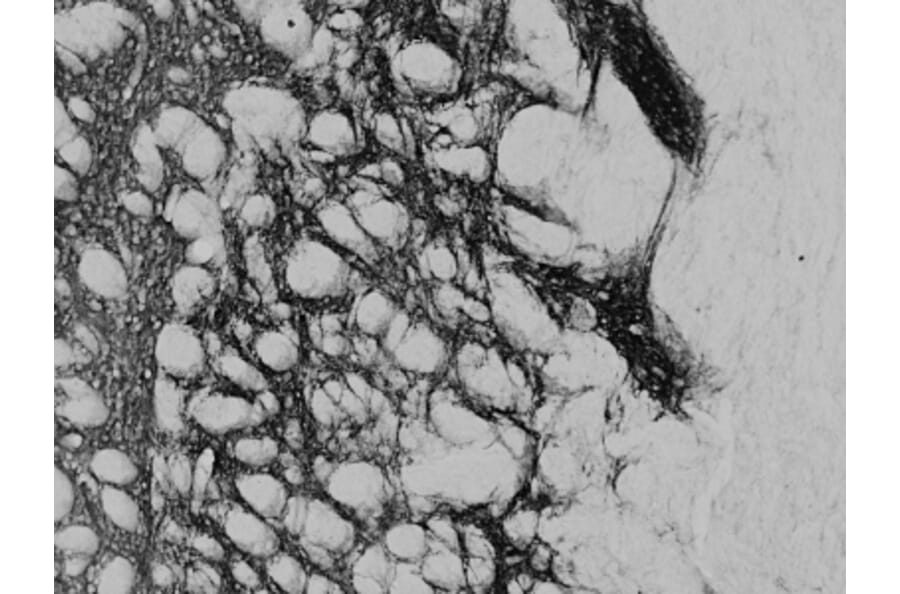

Goat polyclonal antibody to Proenkephalin for ELISA and IHC.

ELISA, IHC

ELISA: 1:32,000, WB: 0.2µg/ml, IHC: 0.02-0.05µg/ml

Mouse, Rat

Synthetic peptide corresponding to the internal region of mouse Proenkephalin.